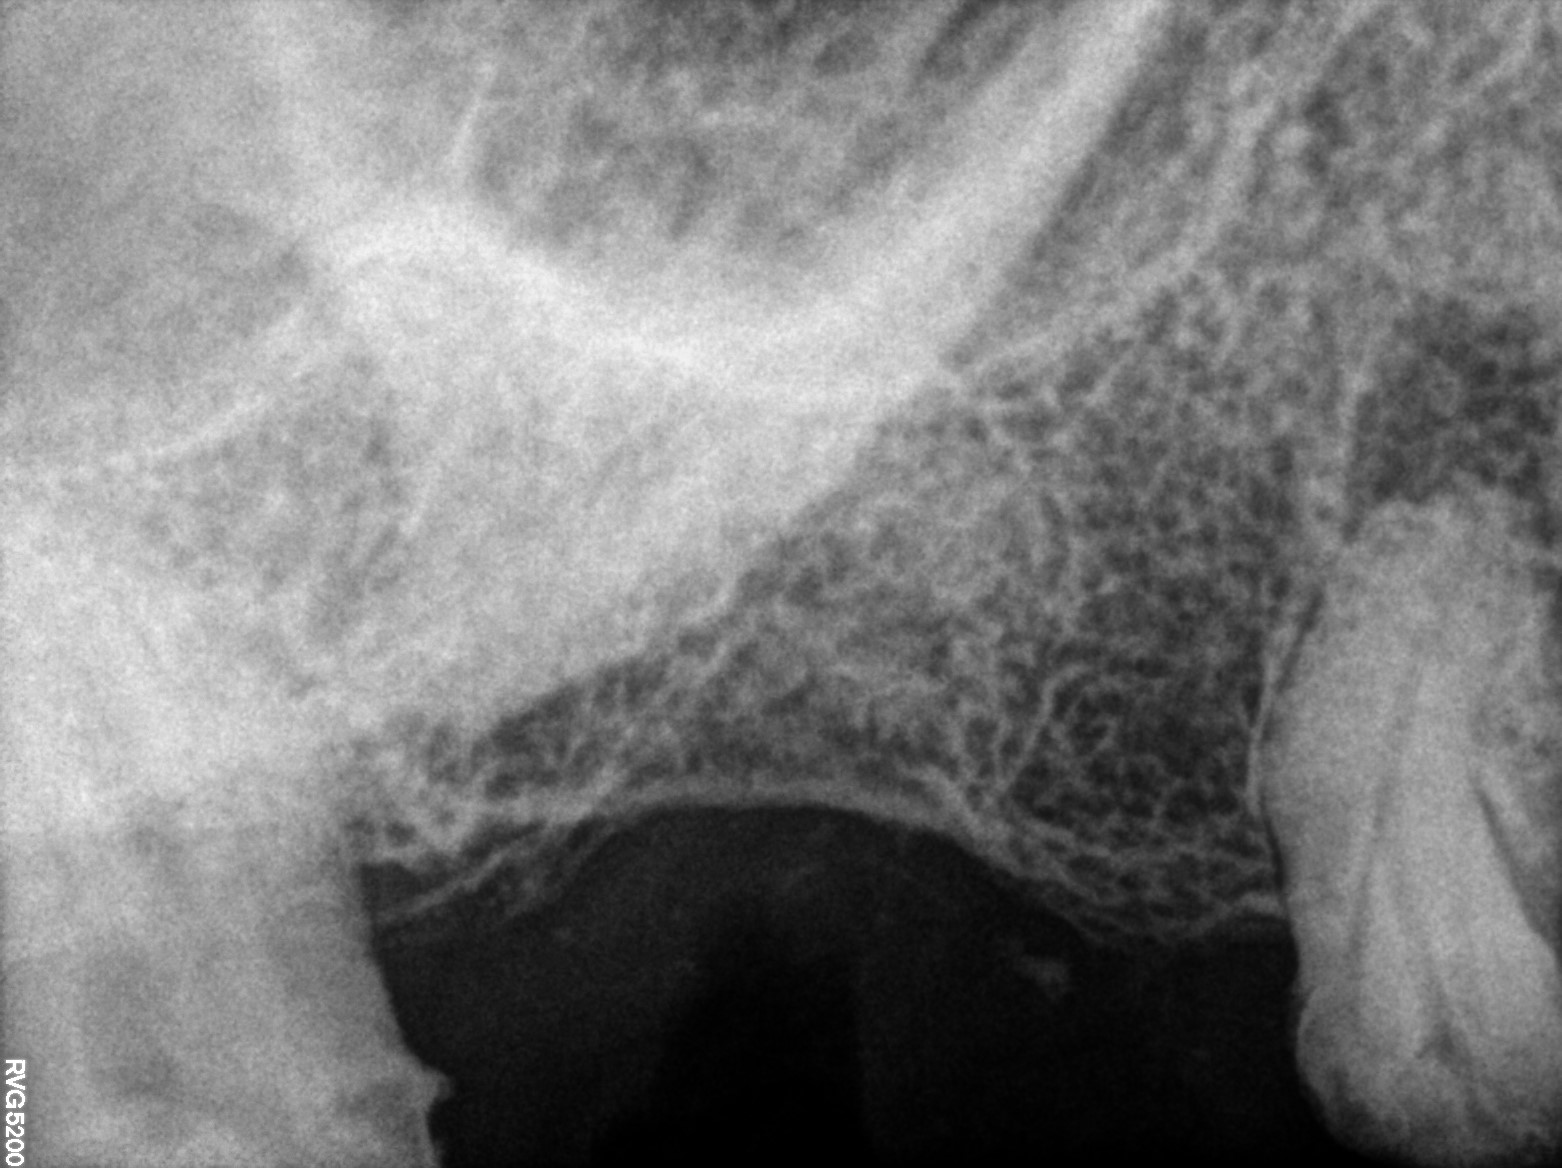

Dental Radiographs FHIR: DocumentReference · LOINC 24641-7

R66.jpg

24641-7